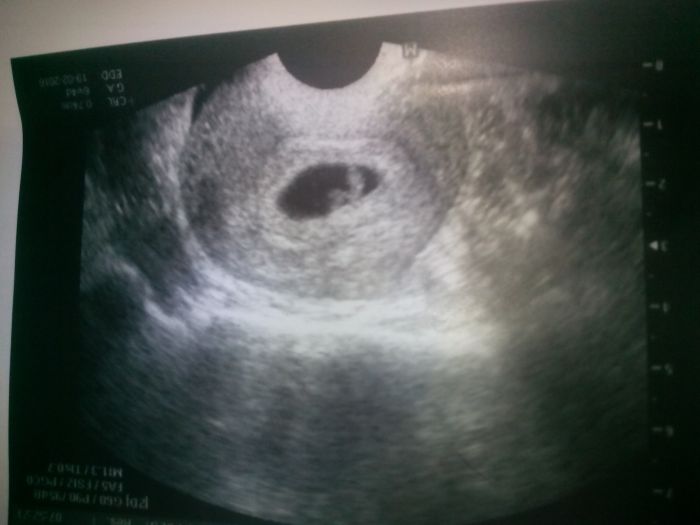

Tak jsem to nevydrzela:-D a sla srdicko bijeee!!!